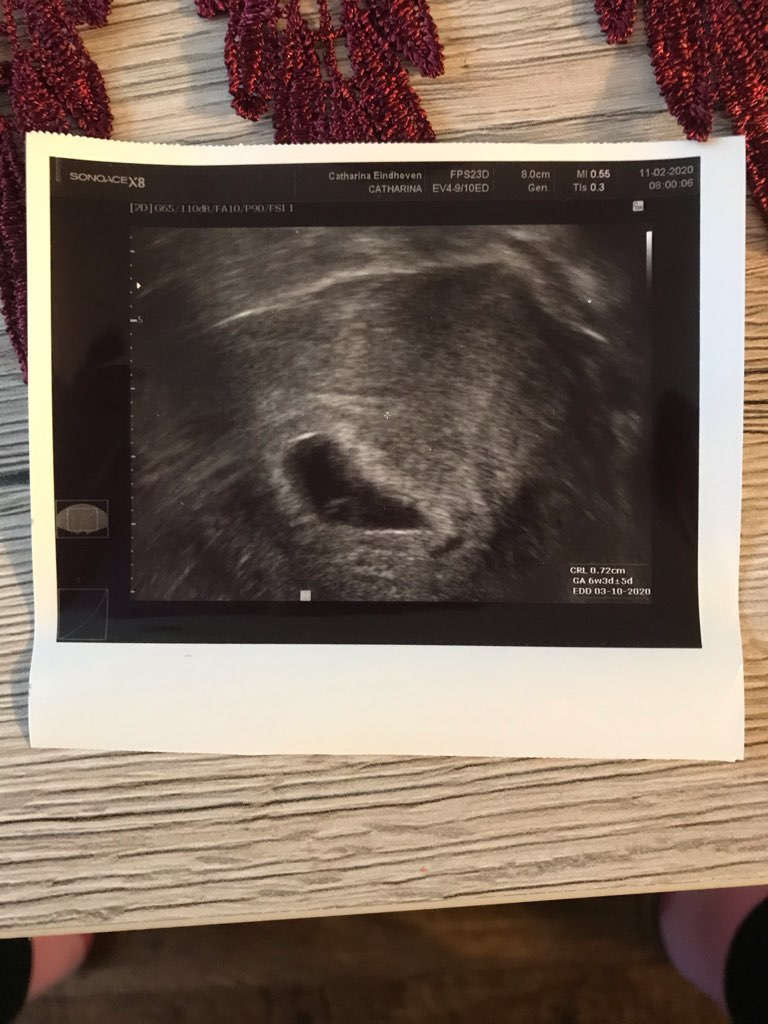

mój nie był jakiś bardzo spłaszczony ale tez była taka kropelka, zdjęcie pierwsze te płaskie z 26dpt, a drugie z 33dpt(dopiero tu było serce)